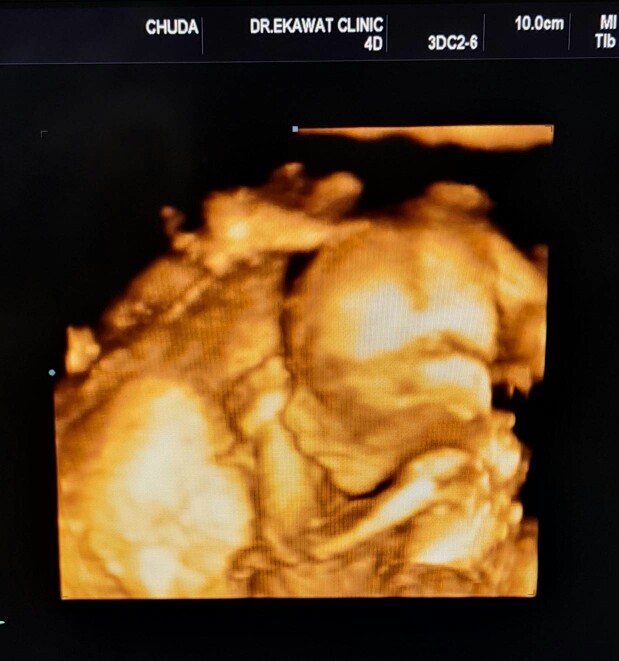

15 สค. 32+5 วีค ค่ะ ผช.

33+2วีค 13สิงหาค่ะ